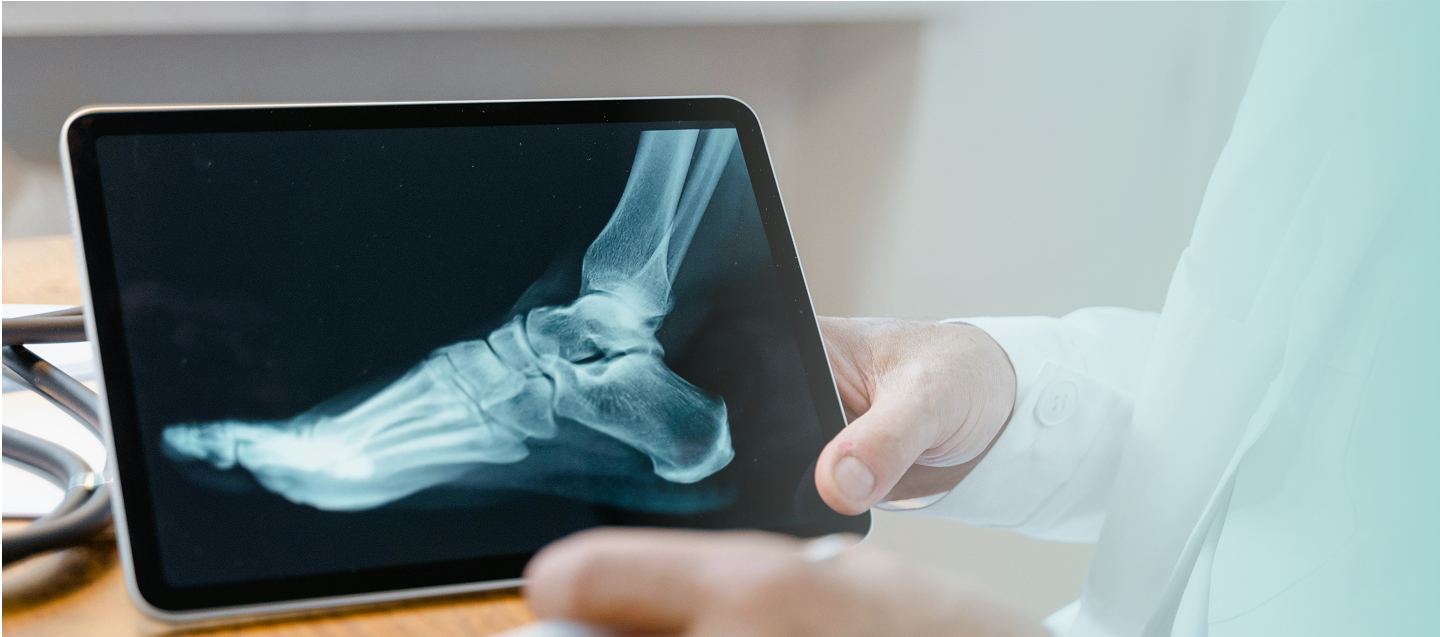

Radiografija je bezbolna i neinvazivna dijagnostička metoda koja se zasniva na primjeni

X zraka za snimanje različitih djelova tijela i organa.

Radiografija se obavlja kao jedan od osnovnih pregleda pri ispitivanju koštano-zglobnog

sistema, kada postoji povreda nekog dijela tela sa sumnjom na prelom kosti, iščašenje

zgloba, istegnuće ligamenata, kada se primijeti deformitet ili otok zgloba ili kosti, kod

pojave bola.